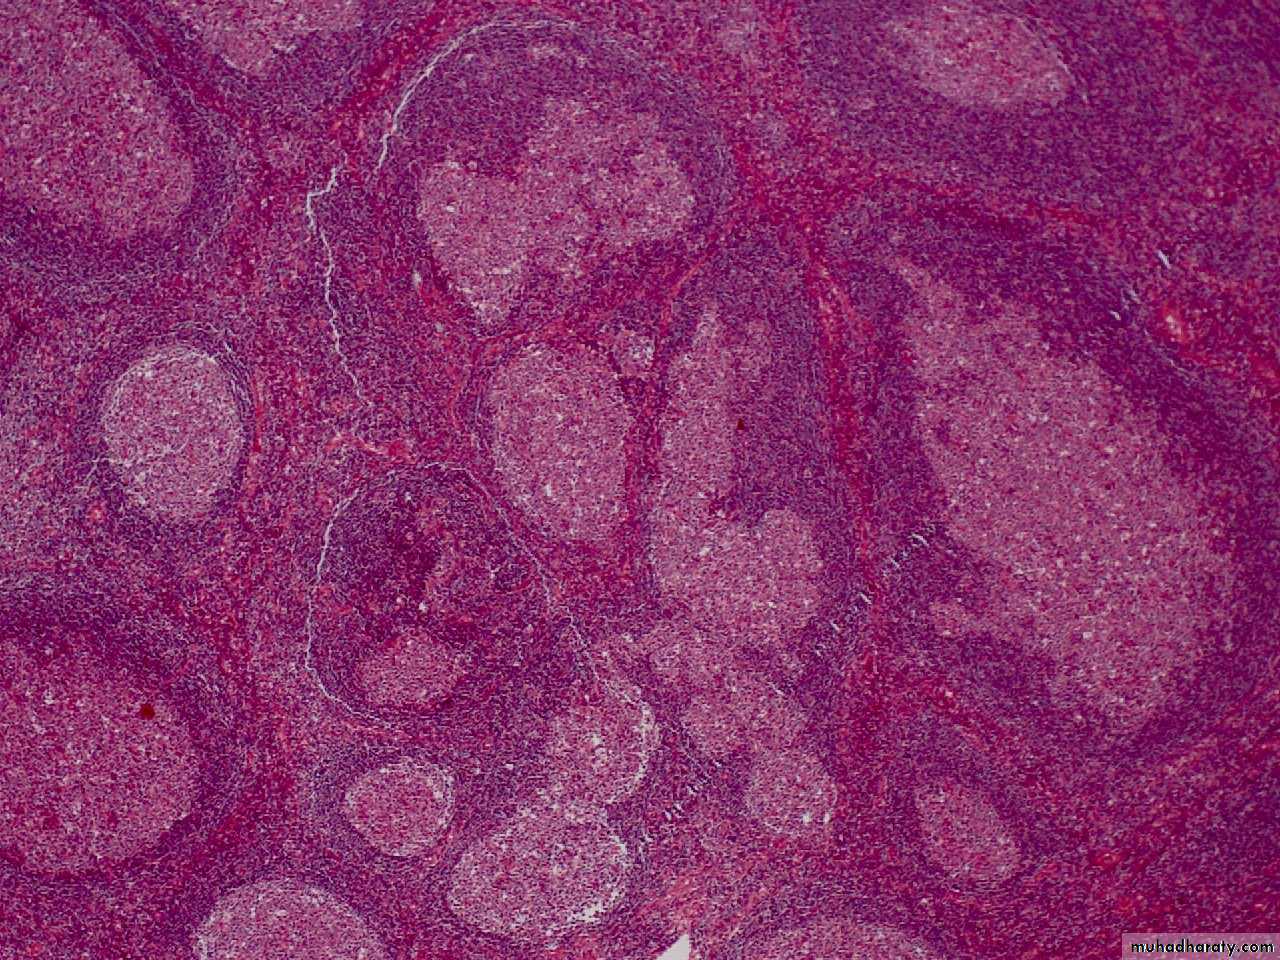

Follicular hyperplasia lymph node LP mic

There is marked differences in size of germinal centers, their well-circumscribed character, and the fact that they are surrounded by a well-defined mantle of lymphocytes